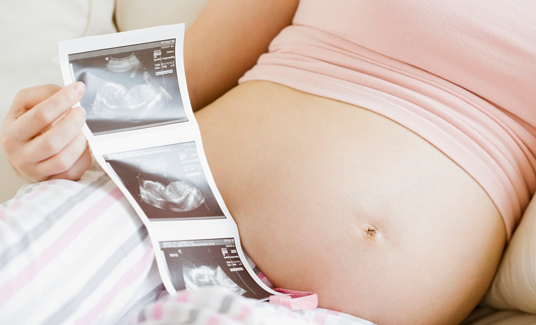

为宝宝留下成长的足迹是每一个准爸妈都想做的事情,准爸妈总是好奇宝宝在肚子里的动态,为了满足准爸妈的好奇心,安徽安琪儿妇产医院引进美国GE—E8四维彩超技术,该技术是目前国际上最先进的四维彩超技术,高清动态的显示胎儿的身体、骨骼、器官的发育情况,并通过高科技技术将宝宝的四维彩超影像刻成光盘,真正的实现零岁动态写真,可供准爸妈随时、反复的观看,为宝宝留下最珍贵的时刻。

宝宝的四维彩超影响还能够刻录成关盘供准妈妈在家欣赏,胎儿的健康也能够促使准妈妈的心情愉悦,准妈妈的心情好了就更有利于宝宝的健康发育,彼此相互依存,相互促进。